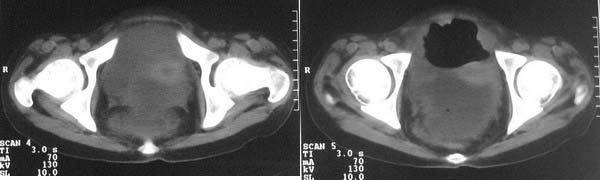

f-18y,腹痛,腹胀,停止排便排气4天,小便正常,四年前阑尾炎手术,病人已手术,明天上传结果。

直肠左侧低密度模糊影,乙状结肠明显扩张,有宽大液平,下腹部肠袢欠规整,内有多发小液平,结合有阑尾炎手术史考虑:直肠周围脓肿,低位肠梗阻,肠粘连。

盆腔巨大脓肿,据术者讲,脓肿大部分壁是有肠管壁形成的,少部分有自己较厚的壁,子宫、附件都泡在脓液里,腹腔肠管广泛粘连,这个病例奇怪的是急性发病,追问不出慢性病史。